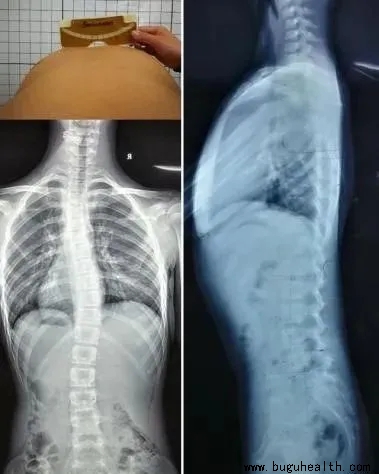

如上图:左边的图是我们正常的脊柱,从后面看应该是一条直线,并且躯干两侧对称。右边的图就是脊柱侧弯,它不仅仅是我们观察到的脊柱向一侧偏移,脊柱侧弯其实是一种脊柱的三维畸形,包括冠状位、矢状位和轴位上的序列异常,分别是:

侧弯

旋转                          平背